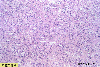

Histology

A case of type Ip+IIc carcinosarcoma of the esophagus with minute invasion to the submucosa.